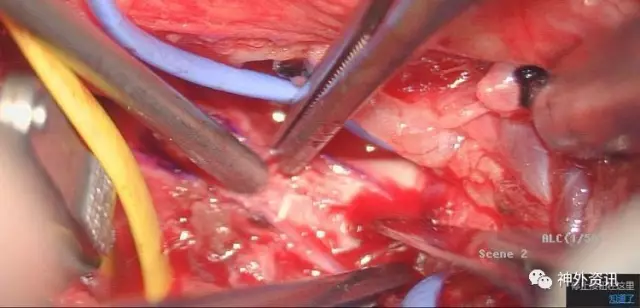

切开外中膜,先切开支架远端管腔,手术的关键是摘除支架,而远端血管通畅我们的手术会更有把握,刀尖切到之处有颅内反向血流溢出

切开外膜你看到了M,亮晶晶的金属支架嵌入增生内膜

支架马上就摘除了,成功在望